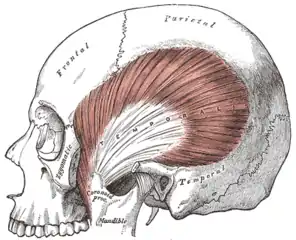

Medial surface The temporalis, with the zygomatic arch and masseter removed

The temporalis, with the zygomatic arch and masseter removed Coronoid process of mandible